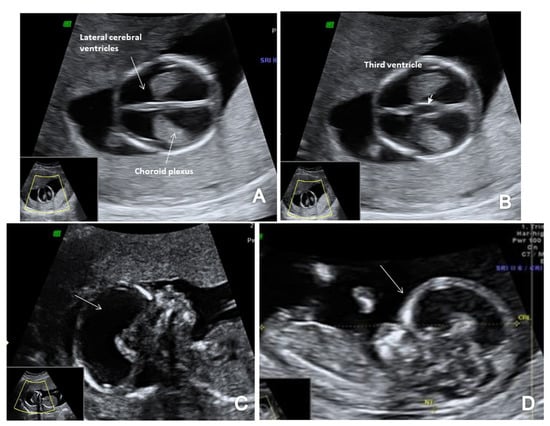

3.1. Spina Bifida

In the axial plane, we noted a decreased intracranial fluid with enlarged choroid plexus in one of three OSB cases while the ‘crash’ sign was obvious in two/three cases. Similarly, in two/three cases of OSB, we noted an abnormal posterior brain (IT, CM and BS/BSOB ratio) (Figure 3 and Figure 4). The single case of meningocele with CSB presented a normal posterior brain anatomy in axial and sagittal view [18]. We found abnormal features of the spine and the overlying skin (kyphoscoliosis, spinal defect or meningocele) in all cases of SB (4/4 cases).

Figure 3.

A case of OSB diagnosed at 12 weeks + 3 days (Case 1): (A) transverse view of enlarged choroid plexus (the ‘dried up’ brain sign, arrow); (B) displacement of mesencephalon and aqueduct of Sylvius and deformation against occipital bone (‘the crash sign’, arrow); (C) mid-sagittal view of the fetal face showing the displacement of BS, which appears thicker (arrow) and with an increased BS/BSOB ratio; (D) sagittal view by transvaginal approach demonstrating the abnormal aspect of the spine—kyphoscoliosis (arrow); (E) specimen presentation of OSB after medical TOP.